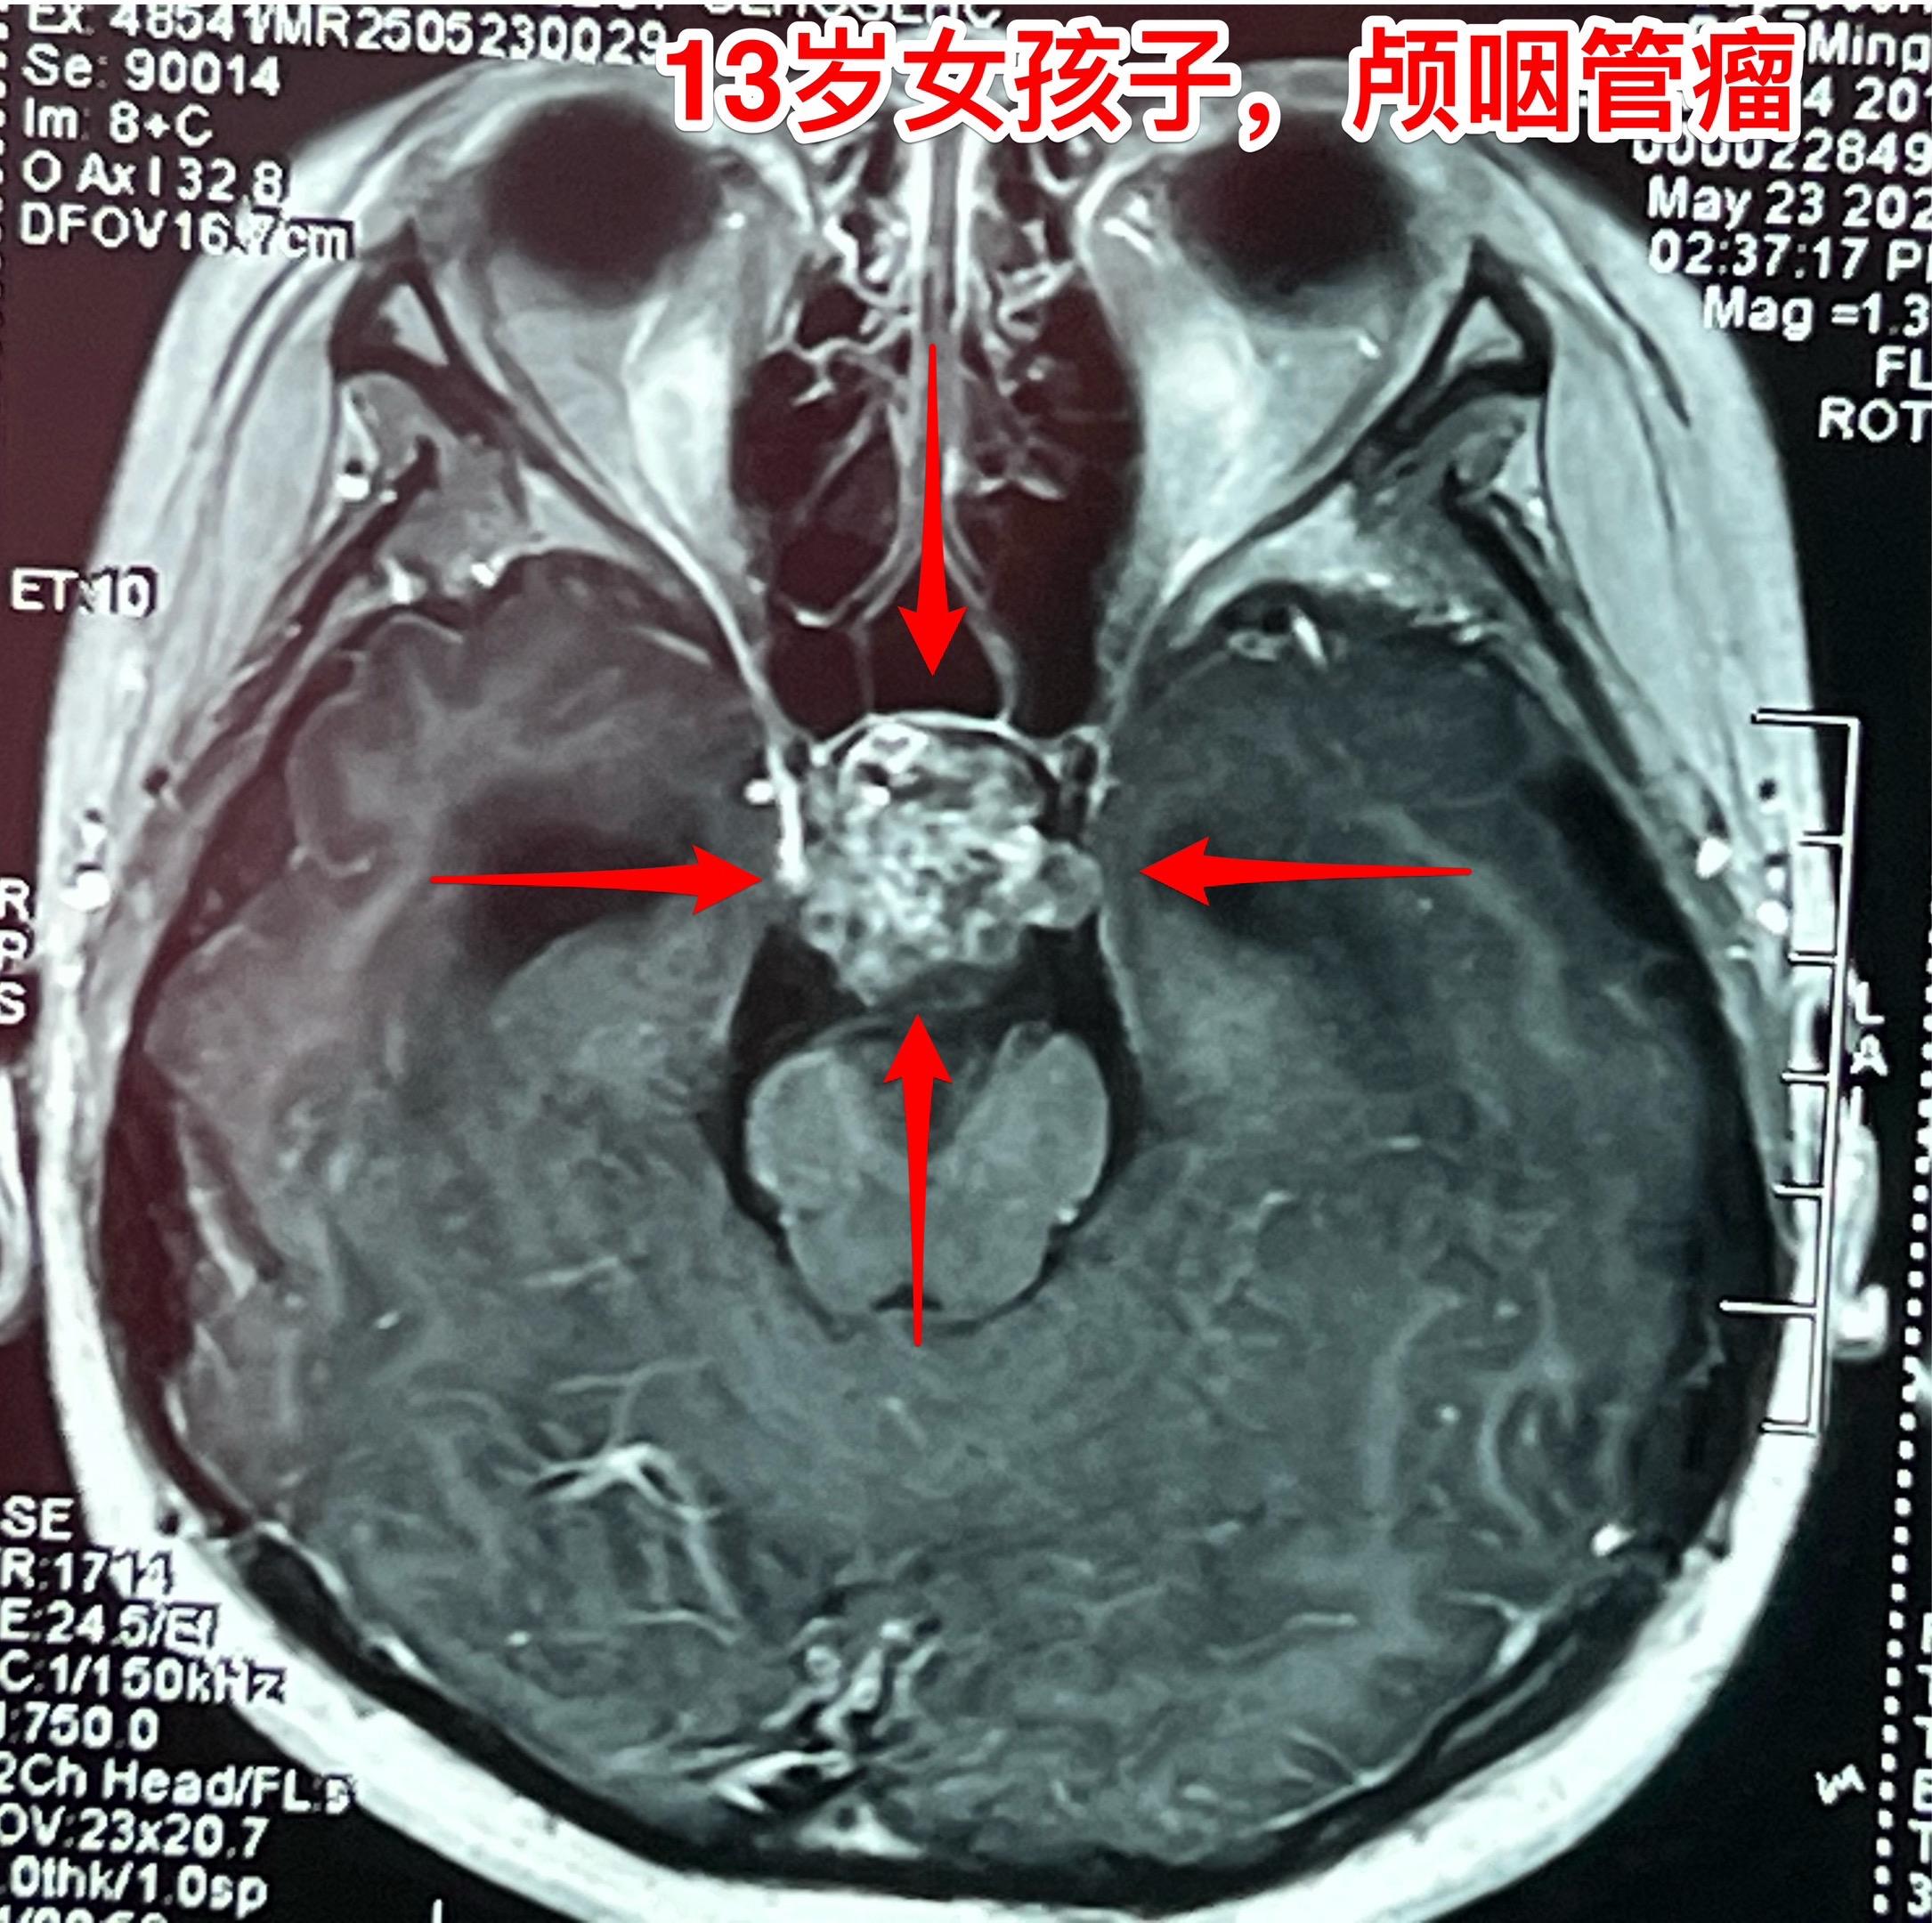

孤独症小孩子5月30日作了颅咽管瘤手术。来自新疆克拉玛依的13女孩子,在2岁时诊断为孤独症,经过家长的不懈努力,加上科学训练,小孩子的生活能力大有改善。 不幸的是,今年小孩子因为头痛、呕吐、行走不利行脑部检查发现了鞍区肿瘤,怀疑是颅咽管瘤,伴有脑积水。在我院住院后经过降颅压治疗、皮质激素治疗,她的头痛、呕吐症状有好转,但是行走不利症状无显著改善。 5月30日作了开颅手术,将肿瘤完全切除。手术后CT结果令人满意。希望她能顺利出院。